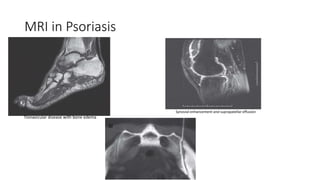

MRI in Psoriasis

Tlonavicular disease with bone edema

Synovial enhancement and suprapatellar effusion

SI

MRI in Psoriasis Tlonaviculardisease with bone edema Synovial enhancement and suprapatellar effusion SI